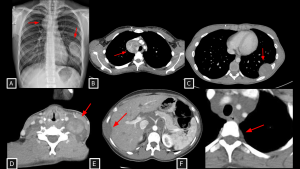

Fig 20: Case 21 – Paravertebral mediastinal metastasis:

A 35-year-old patient with an atypical lipomatous tumor of the right leg (previously operated, with local recurrence demonstrated on MRI (A) developed a heterogeneous solid lesion in the paravertebral mediastinum (arrow in B). The lesion was located anterior and left to the thoracic vertebral bodies and contained foci of fat attenuation (arrows in B and C), consistent with secondary involvement.

SYSTEMATIC APPROACH: 1. Age: Adults / Elderly (History of primary malignancy). | 2. Morphology: Osteolytic bone destruction or conglomerate nodal mass. | 3. Enhancement: Variable (depends on primary). | 4. Relevant Anatomical Relationships: Destroys vertebral body or invades adjacent organs.